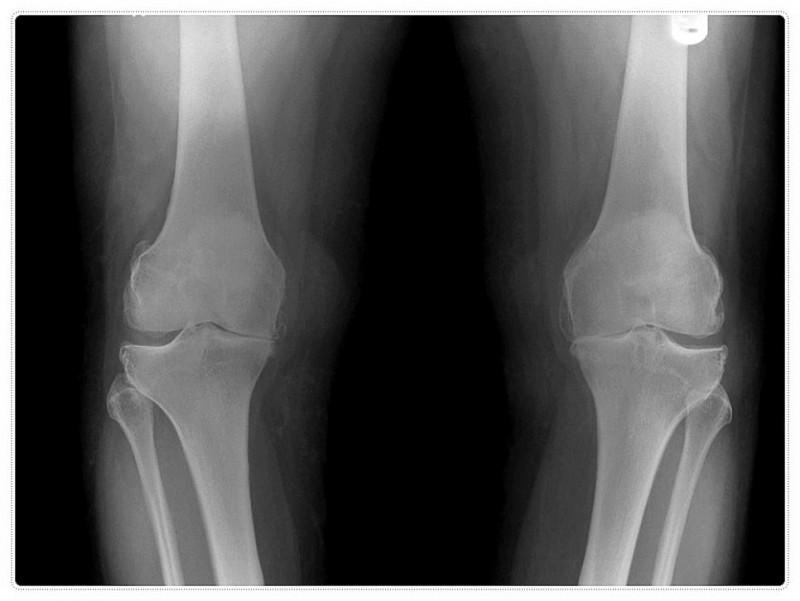

엑스레이 등으로 뼈의 구조적 결함을 확인하고, 한의사의 세밀한 진찰로 인대와 근육의 긴장 상태를 파악하는 것이죠.

- 엑스레이상으로는 큰 이상이 없다는데 정작 본인은 걷기 힘들 정도로 아픔